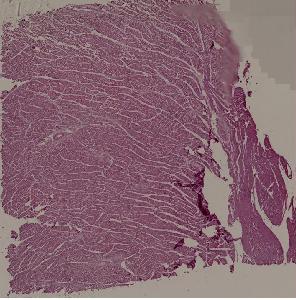

42. Rheumatic pancarditis